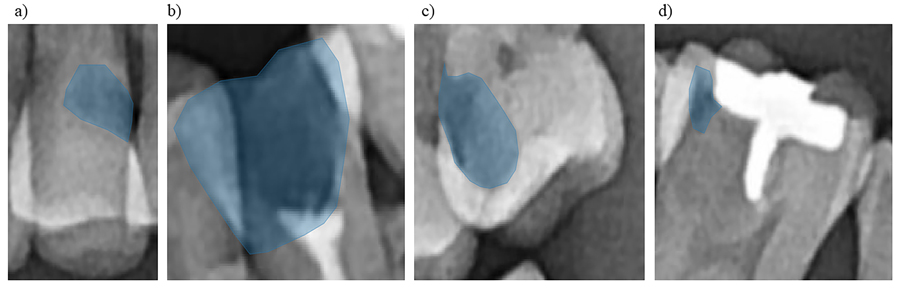

检测过程划分为四步从牙科诊所收集图像为DICOM格式DICOM表示医学数字成像和通信,它是一个国际公认的标准格式,用于查看、存储、检索和分享医学图像第一阶段DISC转换器包括将这些图像转换成PNG格式下位为疾病检测阶段异常点使用训练快进区域神经网络模型物体检测模型检测图像框化区域,那里极有可能出现异常位置验证程序级需要过滤非预设牙类区域内的任何框最后一个步骤是多边形形状器阶段,即预建库二号用于缩小异常符号区间从盒形形到多边形这使牙科医师能够获得高清晰度信息,说明位置和异常类型,以及显示异常特征的确切区域